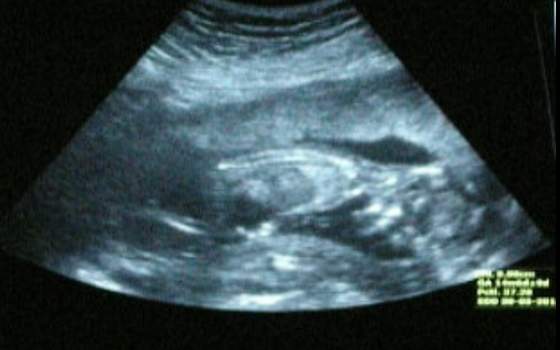

Cieszę się bardzo. Cudne te zdjęcia